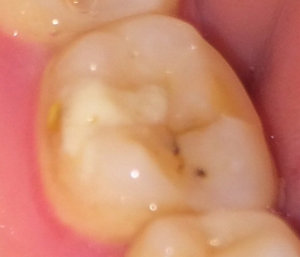

Второй вопрос: Мне вылечили от кариеса семнадцатый и двадцать шестой зубы. Лечение производилось от двух до трех недель назад. До этого жевать было удобно, как твердую, так и мягкую пищу. Сейчас есть мягкую пищу удобно и комфортно, а твердую - не очень. Болей нет, но ощущения не очень приятные. В районе семнадцатого и двадцать шестого, ощущается некий дискомфорт.

С чем это может быть связано?

На снимке в области семнадцатого и двадцать шестого зуба, под пломбой, наблюдается полость, которая неграмотно препарирована перед установкой пломбы, чувствительность и некий дискомфорт при надкусывании или пережевывании твердой пищи связано именно с этим. Что касается шестнадцатого зуба, я считаю, что полость имеется, но все-таки необходим еще и очный прием.